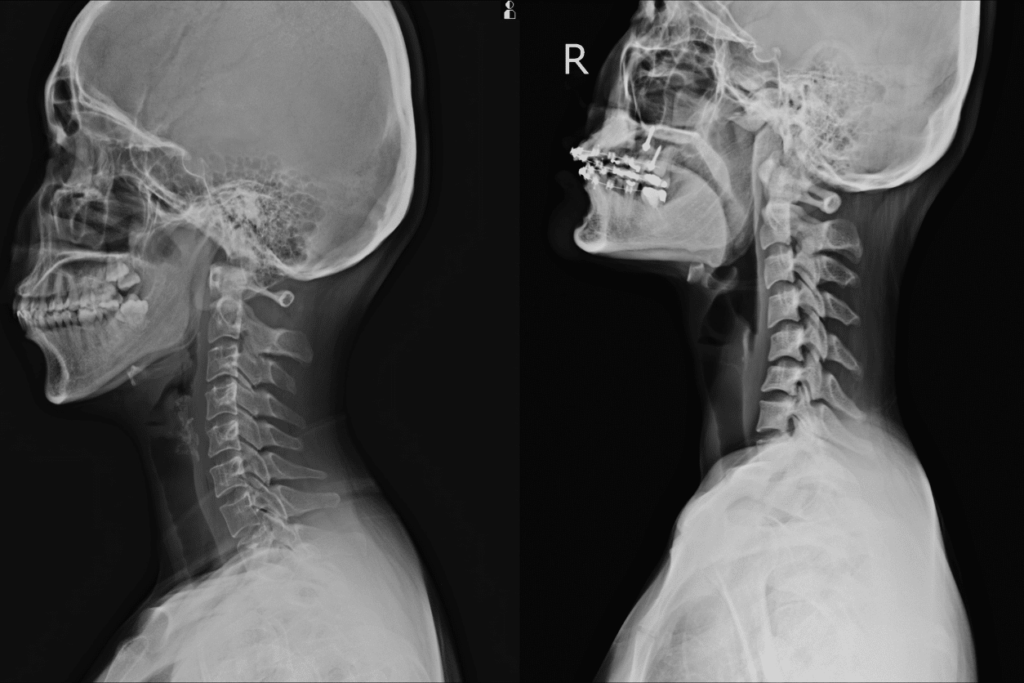

Location of the C4, C5, and C6 Vertebrae

Your spine consists of 33 vertebrae divided into five sections. The cervical region is the topmost section of your spine and includes the first seven vertebrae and the discs that separate them. This region extends from the base of your skull to between your shoulders.

Each vertebra is numbered. Therefore, the designations C4, C5, and C6 refer to the fourth, fifth, and sixth vertebrae in your cervical region.

When you go to the hospital following a car accident, a common practice is for the staff to order X-rays to determine the extent of your injuries. However, herniated discs do not appear on X-rays. Other medical imaging tests, such as MRIs and CT scans, are needed to detect and diagnose herniated discs.